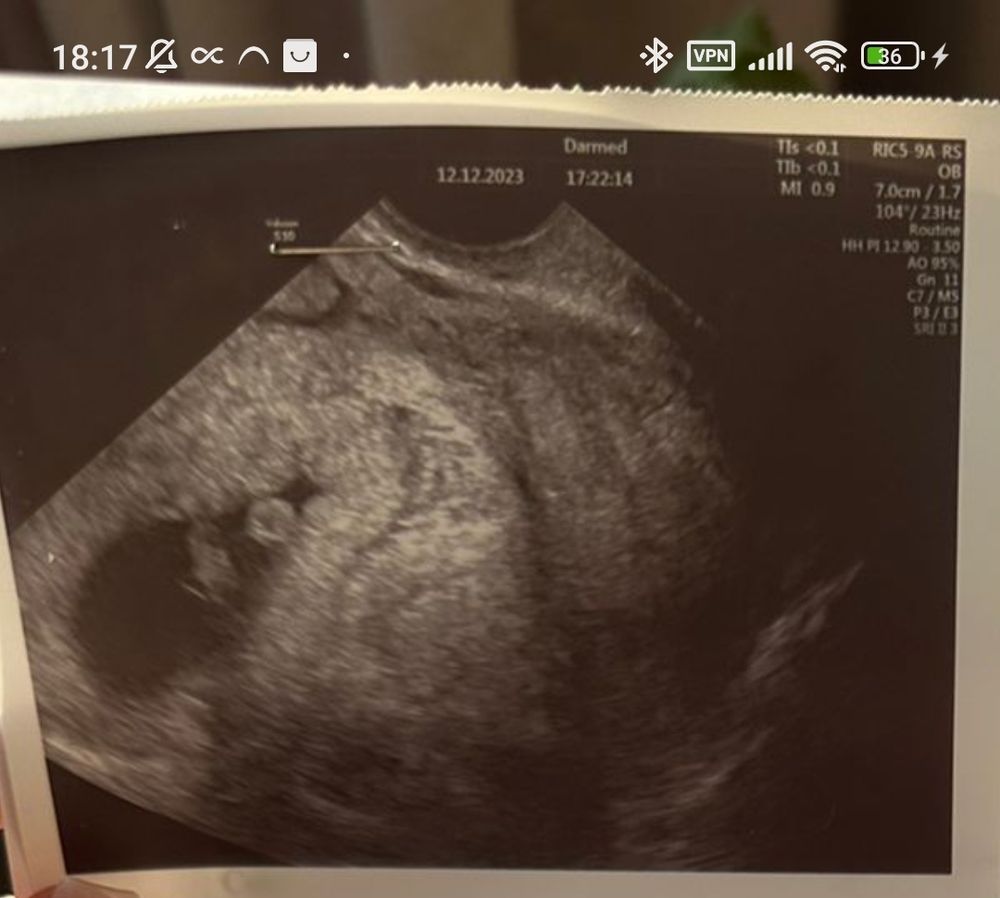

Девочки, снимок с УЗИ, 7 недель, сделано вагинально. Кто разбирается, пол по методу Рамзи?

Натали , в этом методе смотрят снимки УЗИ именно с 6-7 недели. По расположению хориона.